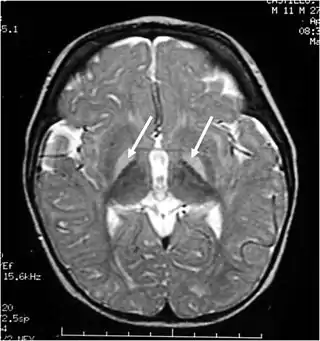

![]() Resonancia magnética de la cabeza. Lesiones hiperintensas de los ganglios basales en T2, marcadas con una flecha blanca. | ||

Macroscópicamente destaca la coloración amarillenta del sistema nervioso central, que se hace más evidente en:

- Los ganglios basales (sobre todo en el globo pálido, el putamen y el núcleo caudado).

- Los núcleos cerebelosos y bulbares, así como en la sustancia blanca y la sustancia gris.